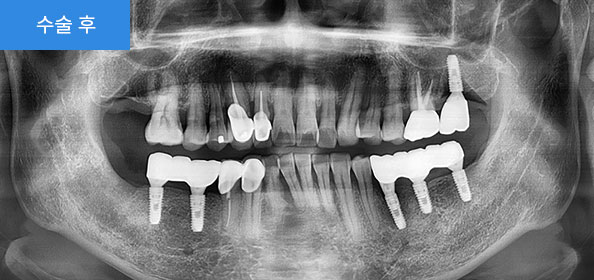

수술 후

2020.06

아랫부분에 틀니를 사용하시다가 불편하셔서 방문하셨습니다.

2021.04

치아가 없는 아랫부분에 네비게이션(가이드)임플란트로, 기존에 뺐다 꼈다 했던 불편한 틀니 대신 좀 더 음식을 잘 씹을 수 있는 임플란트로 진행하였습니다.